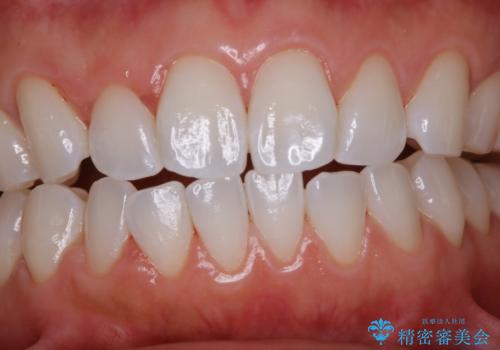

バイオフィルムが除去されると、ご自身本来の歯の表面になります。PMTCをすることで口臭予防にもなり、定期的に行うことが大切です。

- 歯を白くする目的の施術ではありません